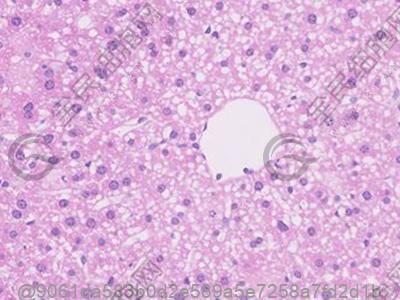

干细胞是人体内的基础细胞,它们能够分化成身体的各种细胞类型,这种特性使得干细胞在医学上有着广泛的应用前景,包括但不限于治疗心脏病、神经退行性疾病、必威国际有限公司、骨关节疾病、皮肤损伤等。